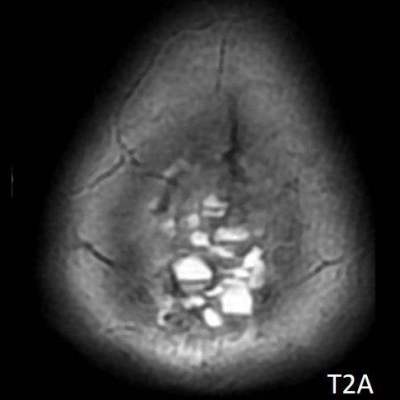

- A) Vertekste, orta hatta, multikistik, T2A sekanslarda yoğun içerikli sıvı-sıvı seviyelenmesi (oklar) ve T1A sekanslarda hiperintens, SWI sekanslarda blooming artefaktı oluşturan, belirgin düşük ADC değerlerine sahip, kanama alanları içeren (oklar) kitlesel lezyon mevcuttur.

- MR görüntülemede genellikle T1 ağırlıklı görüntülerde gri cevher ile izointens, T2 ağırlıklı görüntülerde hiperintens, heterojen kontrast tutulumu gösteren kitlesel lezyon izlenir. Nekrotik, hemorajik, kistik alanlar içerebilir. Kanamaya bağlı sıvı-svı seviyeleri izlenebilir.